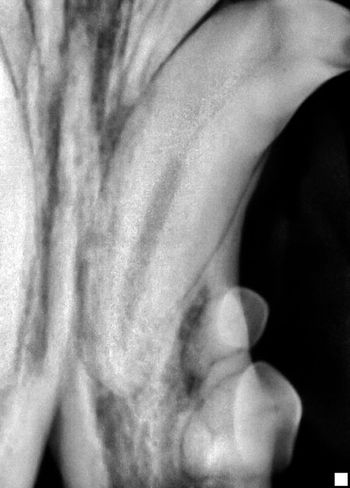

Visual examination, anesthetized probing and intraoral radiography can help veterinarians assess each patient's level of disease.

Visual examination, anesthetized probing and intraoral radiography can help you assess each patient’s level of disease.

According to industry estimates, less than 10 percent of small animal practices have dental radiograph units and of those, less than 10 percent take intraoral films on every dental case.